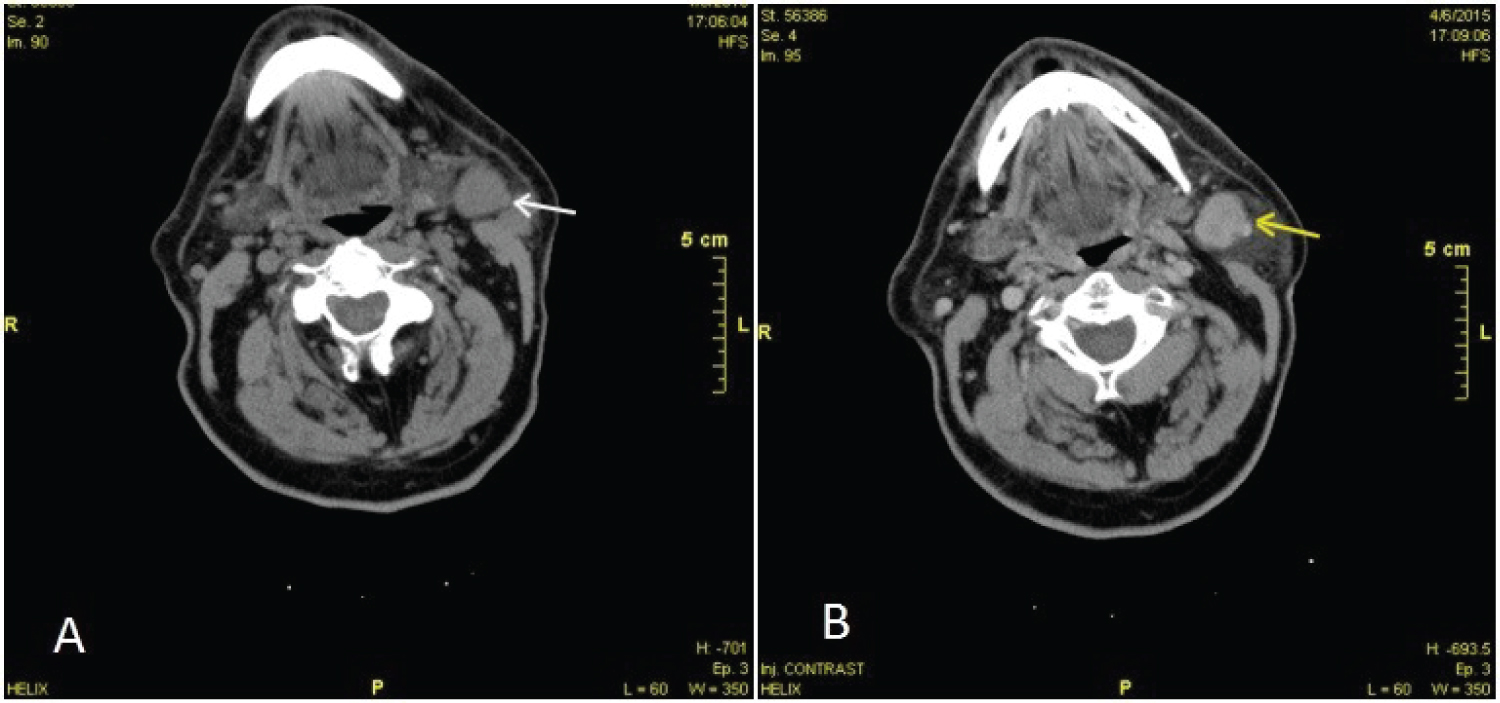

Clinical examination revealed a scleroelastic, firm, painless mass in the left inferior aspect of the parotid gland with ulceration of the overlying skin. Palpation of the neck did not reveal any signs of swollen nodes. Furthermore, other symptoms referring to the patient's general condition (paraneoplastic symptoms) were not mentioned. In the radiological examination with Computed Tomography (CT) scan, a mass of soft tissues was described in the left parotid tail measuring 2.5 × 1.9 cm with no skin involvement. After Intravenous contrast administration the mass was heterogeneously enhanced suggesting areas of central necrosis (Figure 2).

Figure 2: CT scan preoperatively before skin ulceration (A) Before (white arrow) and; (B) after (yellow arrow) intravenous contrast administration. View Figure 2